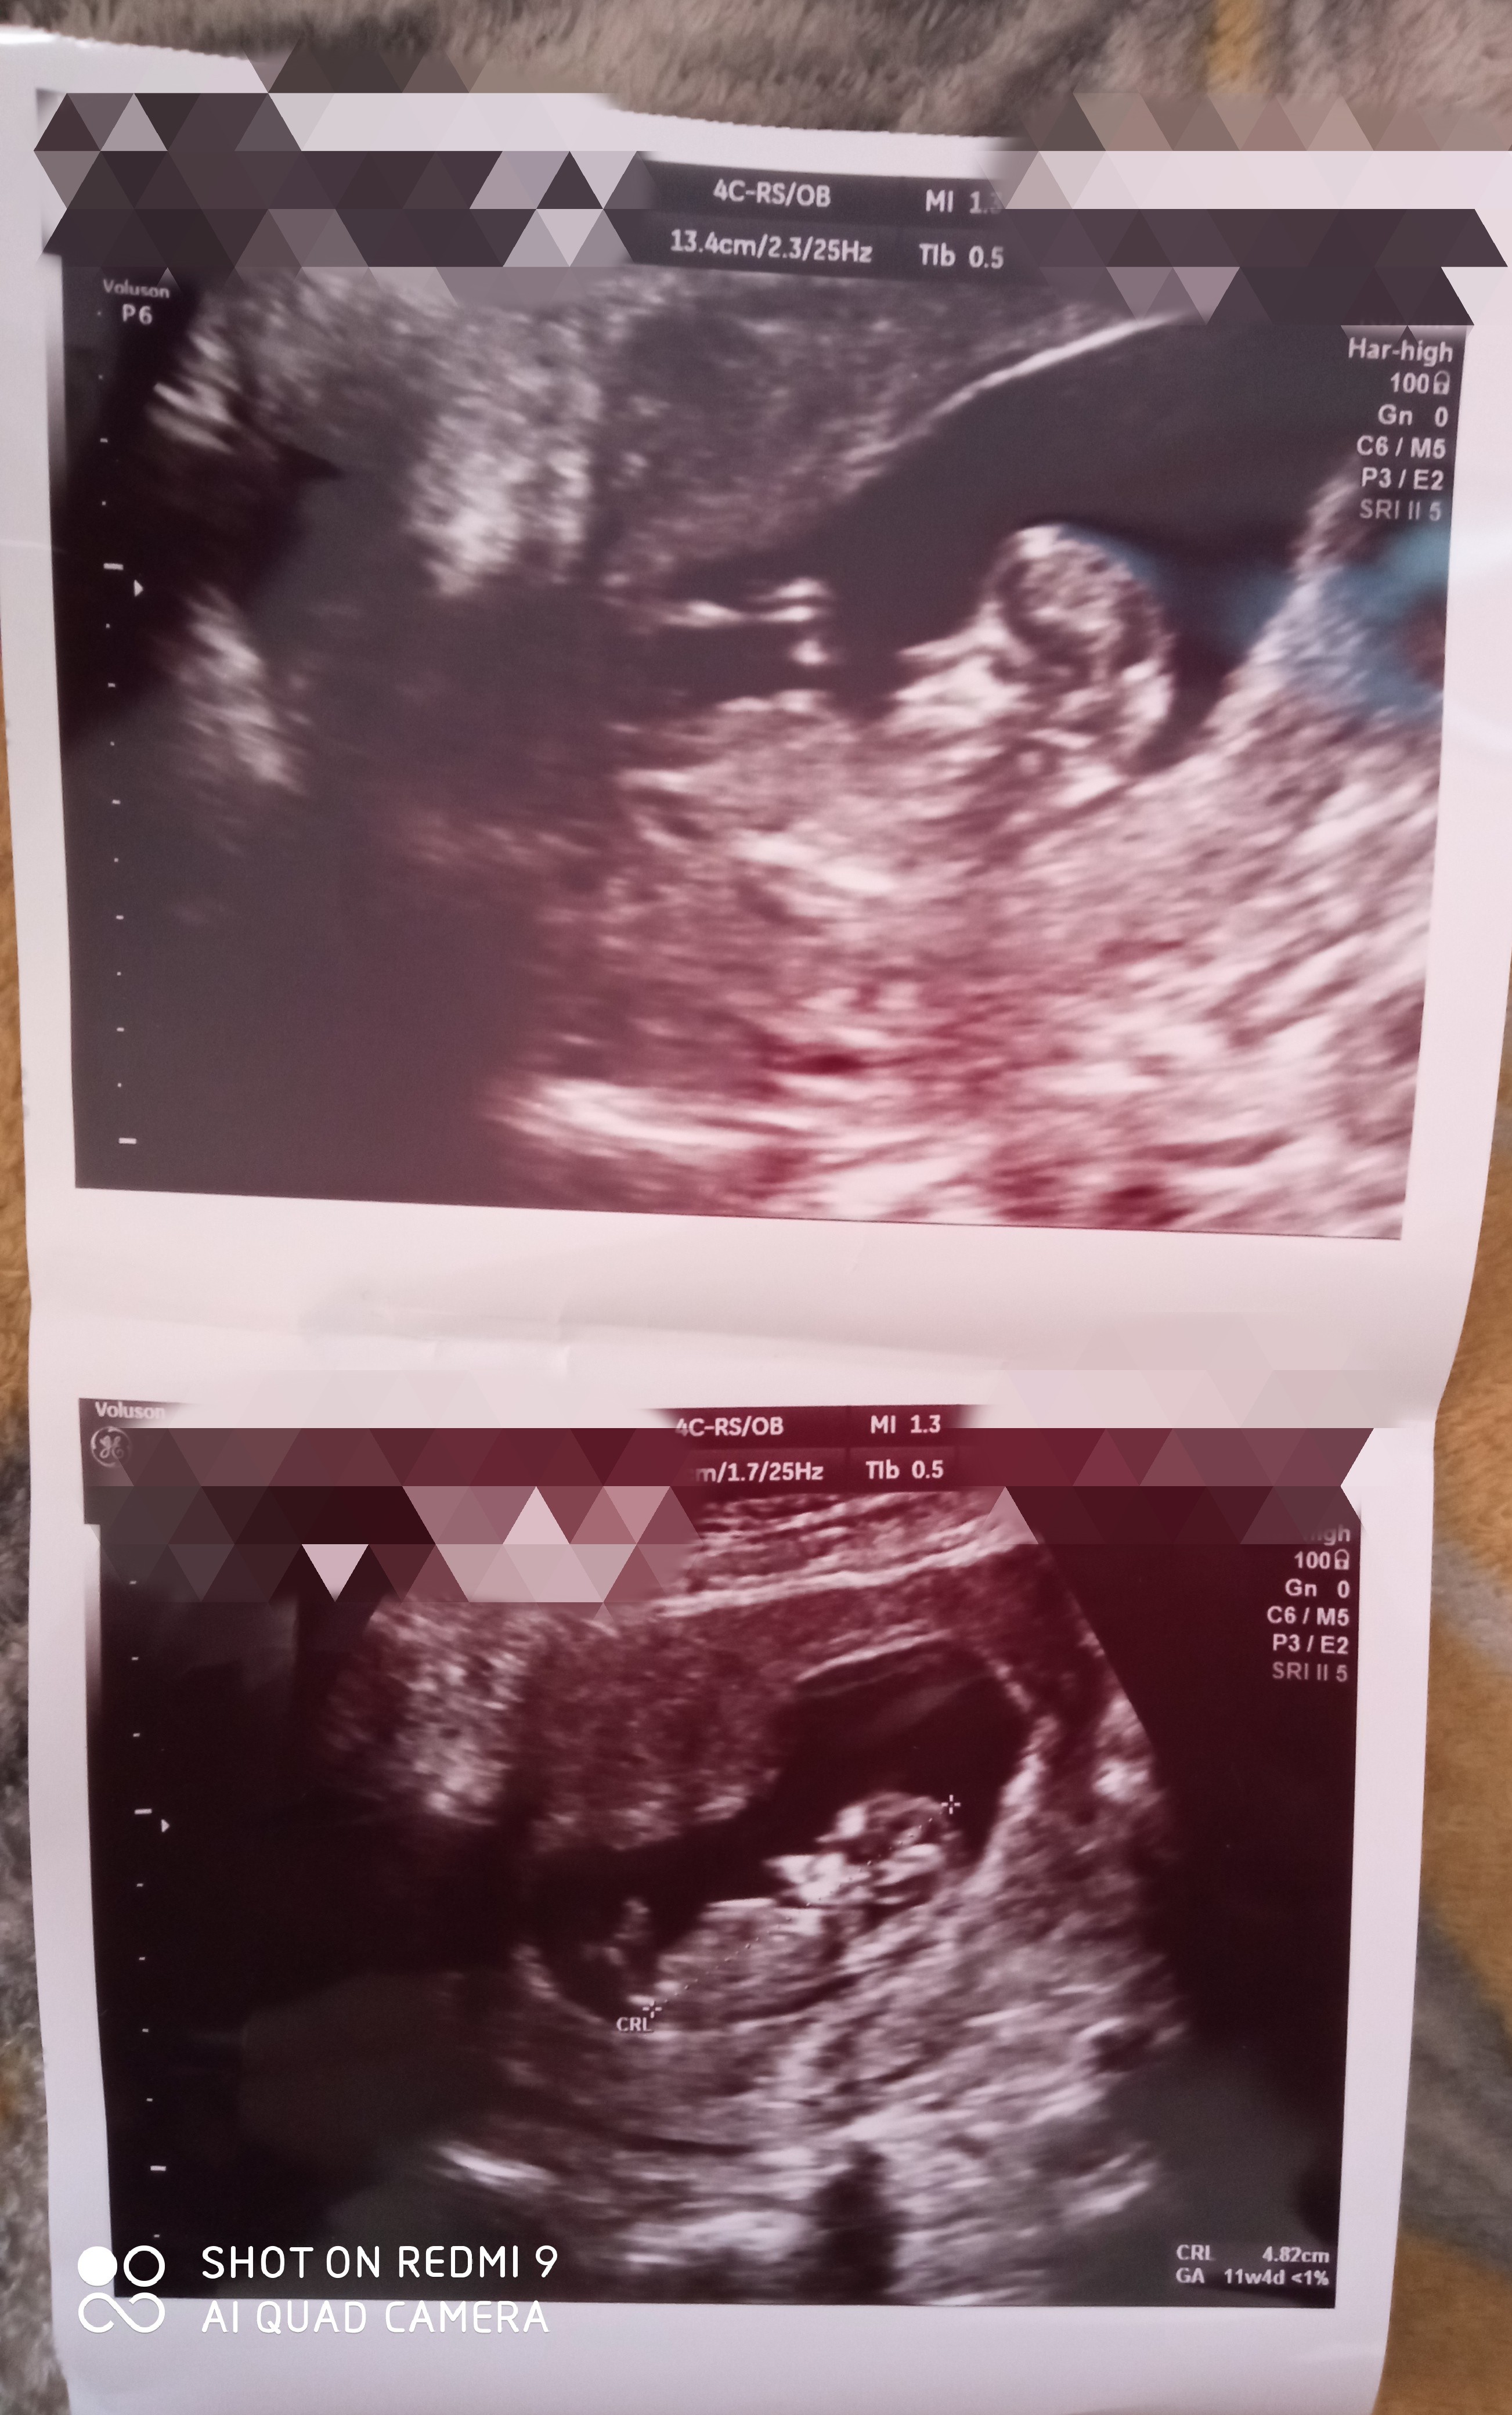

Posyłam Wam mojego maluszka na 90% będzie synek